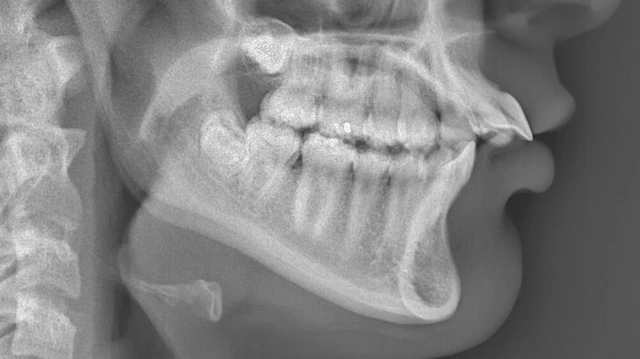

CT ngực độ phân giải cao được xem là tiêu chuẩn xác định giãn phế quản, nhưng trong thực hành lâm sàng hằng ngày, X-quang ngực vẫn là thăm dò hình ảnh đầu tiên và phổ biến. Việc hiểu đúng vai trò của X-quang giãn phế quản giúp bác sĩ sử dụng phương tiện này hợp lý, tránh kỳ vọng quá mức mà vẫn khai thác được giá trị thực tiễn.